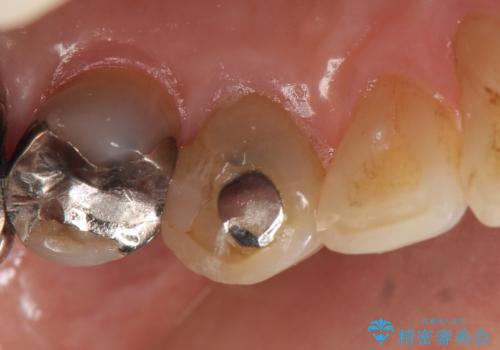

- 他院にて左上3番の被せ物を勧められたが、根管治療からやり直したいと当院にいらっしゃった方の症例です。

再根管治療後、オールセラミッククラウンによる補綴を行いました。

- オールセラミッククラウン…¥100,000、仮歯…¥10,000、ファイバーコア…¥20,000、精密根管治療費別途費用は治療当時の料金となります